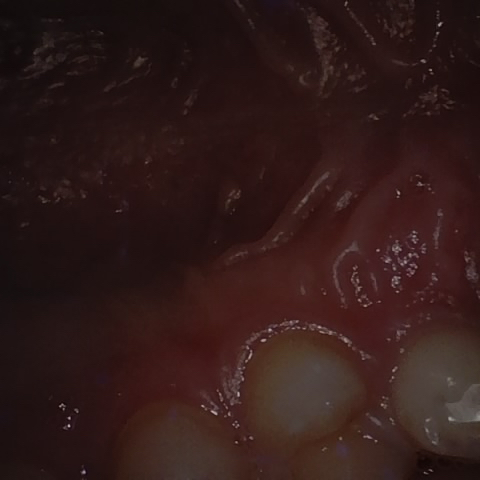

Image 93 / 121

NHD30676

Annotated as "Good"